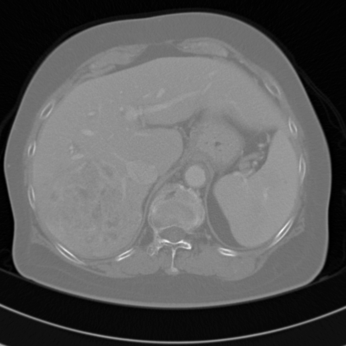

In this paper, we explore automatic classification methods of computed tomography (CT) scans of hepatic (liver) lesions. We have a dataset of CT scans of 132 hepatic lesions along with an outline, diagnosis, and semantic descriptors of the lesion provided by a radiologist. There are nine lesion types represented in the data, with the vast majority of the lesions (90 lesions) evenly split between cysts and metastases, followed by hemangiomas (18 lesions), hepatocellular carcinomas (HCC, 11 lesions), focal nodules (5 lesions), abscesses (3 lesions), neuroendocrine neoplasms (NeN, 3 lesions), a single laceration and a single fat deposit.

It has been demonstrated that semantic features are useful for classification in hepatic lesions [13]. This indicates that visually identifiable structures exist within the lesions, but it has been difficult finding quantitative methods of defining these structures. For example, consider the six images in Figures 3 and 4. The first three show the abscesses contained in our dataset. The second three show hemangiomas (deformations of blood vessels). The abscesses present what is called ‘cluster of grapes’ morphology. But the arrangements of this structure (the clusters of grapes) are very different in each lesion. Similarly, the hemangiomas show the characteristic large dark central region with dense white regions on the outer edge of the lesion. Yet, the hemangiomas lack a rotational orientation, different numbers of the two region types exist and the formations vary in size and shape. The qualitative nature of these observations has made it difficult to find quantitative measures of the structures.